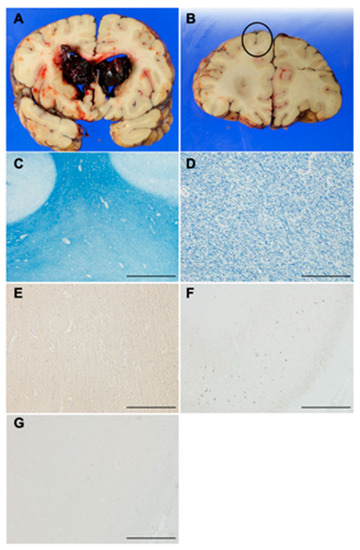

3.9. Histopathological Characteristics of an Autopsy Brain